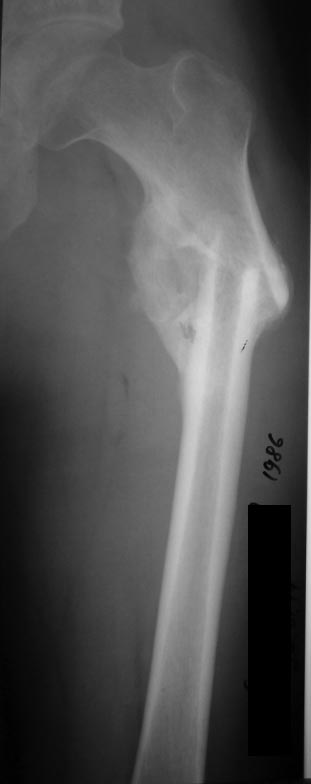

Уважаемые коллеги! Предоставляем один свежих случаев, если что то не так просим строго не судить! С уважением Ерсин Жунусов

... Вы, конечно, сделали гораздо лучше, чем было до операции. Просто несоблюдение 1-го правила остеотомий (а следом и 2-го) и привели именно к подобному расположению гвоздя и к остаточной деформации. + не вполне ясен подобный вариант блокирования проксимального фрагмента.

Отправитель: Lev Lapidus 21 Май 2014, 05:57

Извините, но здесь нет удлинения. Просто восстановлена прежняя длина бедра.